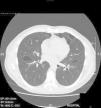

Varón de 35 años, no fumador y con antecedentes patológicos de hipertensión arterial y asma bronquial que ingresa en urgencias por dolor escapular derecho de una semana de evolución. La radiografía de tórax revela un neumotórax derecho completo sin otras alteraciones pulmonares, por lo que se coloca un drenaje torácico y evoluciona favorablemente. A los 30 días presenta un nuevo episodio de neumotórax derecho completo por lo que se indica una videotoracoscopia derecha en la que se observa la presencia de pequeñas bullas apicales que se resecan, más abrasión mecánica pleural del tercio superior del hemitórax. El paciente evoluciona favorablemente y es dado de alta hospitalaria a los 3 días postintervención. El resultado del estudio histológico es compatible con presencia de bullas enfisematosas. Cuatro años más tarde ingresa nuevamente en urgencias por un cuadro de dolor pleurítico izquierdo diagnosticándose de un neumotórax izquierdo completo. Se lleva a cabo una TAC torácica que informa del neumotórax más la presencia de múltiples cavidades quísticas bilaterales de tamaño significativo y predominio basal (fig. 1). Dado el antecedente de un neumotórax contralateral intervenido se realiza una videotoracoscopia izquierda, resecándose la porción apical del ápex más abrasión mecánica pleural del tercio superior del hemitórax. El estudio histológico del ápex pulmonar resecado es compatible con la presencia de bullas enfisematosas, sin otras alteraciones. El paciente evoluciona favorablemente siendo dado de alta a los 3 días. Dos años más tarde reingresa por cuadro de recidiva completa de su neumotórax derecho, por lo que se practica una nueva videotoracoscopia derecha, realizándose una pleurodesis química con 8g de talco. Ante el carácter recidivante y bilateral de los episodios de neumotórax con la presencia en la TAC de quistes bilaterales se realiza un estudio clínico completo, en el que llamaron la atención unas discretas lesiones cutáneas papulosas de aspecto microquístico en la región frontal del paciente las cuales se biopsian con resultado histológico de fibrofoliculomas. La presencia de neumotórax bilaterales de repetición, cavidades quísticas pulmonares bilaterales y fibrofoliculomas cutáneos hace sospechar la posibilidad de un SBHD, por lo que se llevó a cabo estudio en sangre periférica del gen FLCN, cuyas mutaciones se asocian con la aparición de este síndrome, se detectó un cambio en el exón 11 del gen FLCN en la posición 1285 consistente en la deleción de una citosina. Este cambio supone la introducción de un codón de parada prematuro y el consiguiente truncamiento de la proteína. Dada la asociación del síndrome con tumores renales se realiza una TAC abdominal que es normal. El paciente no ha presentado recidiva de sus neumotórax hasta el momento. Se solicitó un análisis histológico más exhaustivo de las muestras de tejido pulmonar obtenido en las 2 primeras intervenciones quirúrgicas. El nuevo informe confirma que las bullas pulmonares tanto del ápex derecho como del izquierdo están rodeadas por paredes alveolares normales y que protruyen en los septos interlobulillares, estas características histológicas se han descrito (junto a la presencia de septos intraquísticos y a la profusión de vénulas en el espacio quístico) como características del SBHD4.

El SBHD es una rara genodermatosis de herencia autosómica dominante caracterizada esencialmente por la presencia de fibrofoliculomas y/o tricodiscomas cutáneos, quistes pulmonares, neumotórax espontáneos y tumores renales. El gen implicado en este síndrome —FLCN—, codifica la foliculina, que se expresa preferentemente a nivel cutáneo, renal y pulmonar5. Los criterios mayores para el diagnóstico del SBHD son las mutaciones del gen FLCN en el estudio genético más la presencia de las lesiones cutáneas (fibrofoliculomas o tricodiscomas)6. Dentro de las manifestaciones extracutáneas las más frecuentes son las neumológicas: hasta un 80% de los pacientes con SBHD presentan quistes pulmonares, que pueden ser asintomáticos durante años7. El número y tamaño de las lesiones varía de un paciente a otro, oscilando desde quistes de pequeño tamaño a bullas de varios centímetros, localizadas sobre todo en las bases pulmonares y a nivel subpleural. Se ha visto una relación entre el mayor tamaño y volumen de los quistes y el mayor riesgo de desarrollar neumotórax. Entre los pacientes que presentan quistes pulmonares, aproximadamente un 20-30% presentan historia de neumotórax, siendo el número medio de 2 episodios. Además, cuando se estudian los pacientes con historia de neumotórax la gran mayoría presentan quistes pulmonares múltiples. El pulmón más afectado suele ser el derecho, aunque pueden afectarse ambos hasta en un 23% de los casos8. Un reciente estudio ha hallado que el 5-10% de los neumotórax espontáneos primarios estarían relacionados con un SBHD9. La fisiopatología de los quistes pulmonares es desconocida, la teoría más actual es la «stretch hypothesis»10 que sugiere que el origen de los quistes podría estar en los defectos de adhesión celular generados por la mutación. Con el tiempo la expansión pulmonar repetida «sobre-expande» el espacio alveolar especialmente en las regiones pulmonares con mayores cambios en el volumen alveolar. La TAC torácica es la exploración óptima para el diagnóstico de la afectación pulmonar11,12.